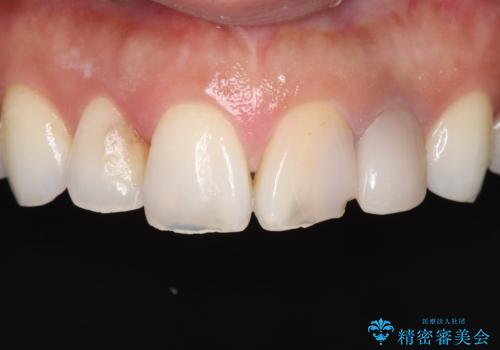

- 上顎の前歯4本が、過去の治療痕による変色や欠けで見た目が気になるとの主訴でご来院されました。患者様は、思い切り笑えるよう自然で美しい前歯を求めていらっしゃいました。そこで、最も天然歯に近い審美性を再現できるオールセラミッククラウンを用いた治療計画を立案しました。歯並びや色のバランスを整え、長期的に安定する美しい口元を獲得することを目指します。